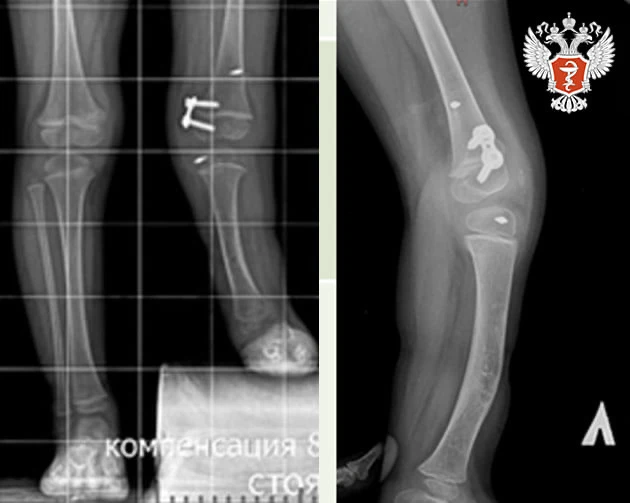

🧍‍♂ Михаил Мурашко: Ортопедия — одно из направлений медицины, которое позволяет человеку чувствовать себя активным и получать удовольствие от жизни

Об этом заявил министр здравоохранения РФ Михаил Мурашко в ходе выступления на XII Всероссийском Приоровском форуме, посвященный 140-летию со дня рождения НМИЦ травматологии и ортопедии им. Н. Н. Приорова Минздрава России.

— Ортопедия является, по сути, одним из основополагающих направлений, наряду с когнитивным здоровьем. Именно эти два момента позволяют человеку чувствовать себя активным, полноценным гражданином и получать от жизни удовольствие, — рассказал он.

➡️ Михаил Мурашко подчеркнул стратегическую роль ортопедии в рамках национальных проектов, направленных на увеличение продолжительности здоровой жизни.

Также министр отметил положительные тенденции в отрасли ортопедии:

➡️ Увеличение объема оказываемой помощи;

➡️ Расширение технологий с использованием роботизированных методов;

➡️ Повышается качество эндопротезов.

— Хочу отметить, что НМИЦ травматологии и ортопедии им. Н. Н. Приорова Минздрава России всегда были приверженцами и последователями системы менеджмента качества, позволяющие расширять и внедрять новые технологии, обеспечивая их безопасность для пациента, — рассказал он.

Особое внимание Михаил Мурашко уделил роли благотворительного фонда «Круг добра» в финансировании высокотехнологичной помощи, в том числе уникальных операций для детей.

— Все эти возможности появились благодаря тому, что фонд «Круг добра» слышит нас. Для развития ортопедии у нас сегодня есть и материально-технические базы, и источники финансирования, — отметил он.